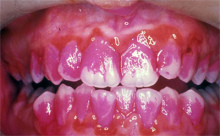

Fehlstellungen der Zähne können Karies provozieren

oder Infektionsherde bilden, weil die Zähne mit der

Zahnbürste dann z.T. nicht mehr zugänglich sind [8].

-- starke Entzündung und Fieber [6].

-- Engstände der Zähne können Karies provozieren oder

Infektionsherde bilden, weil die Zähne mit der